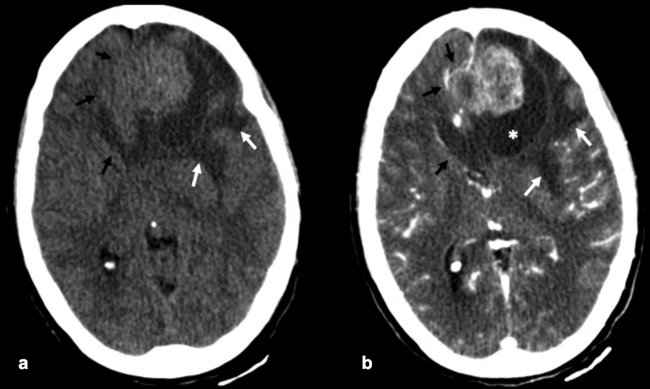

La TC de corte fino (espesor de corte de 1 mm) con reconstrucciones en plano coronal y sagital, es la mejor prueba de imagen inicial para el estudio del NBO. En la TC, aparece como una masa homogénea de tejido blando en la bóveda nasal con realce moderado y uniforme (►Figs.1y2). Se pueden encontrar calcificaciones punteadas dispersas (►Figs.2,3,4,5a,6).50 El valor principal de la TC es una mejor definición de la afectación ósea en comparación con la RM. La TC ayuda a evaluar la erosión ósea de la placa cribiforme, la fóvea etmoidal y la lámina papirácea (►Figs.1,2,3,4,5a,8). Sin embargo, la remodelación ósea sin erosión puede presentarse en algunos casos debido a su patrón de crecimiento indolente.3,35,49 Los estudios de TC generalmente revelan un patrón lítico y muy raramente hiperostosis dominante que simula displasia fibrosa.51 La TC también es útil para evaluar la presencia de metástasis regionales en cuello y a distancia.52,53

La RM es la prueba de imagen de elección para evaluar los detalles de la extensión y la estadificación locorregional del tumor. La RM es superior a la TC para determinar el grado de afectación del tejido blando (►Fig. 9) con una mejor evaluación de la afectación intracraneal (►Figs.10,11,12,13,14), orbital (►Figs.14y15), de la base del cráneo y la invasión perineural.53,54 La RM tiene un valor añadido para distinguir la afectación dural de la del parénquima cerebral (►Fig. 12).55 En la RM, el NBO aparece hipointenso respecto a la sustancia gris en imágenes ponderadas en T1 y de isointenso a hiperintenso en las imágenes ponderadas en T2 (►Figs.10,11,12,13,14,15).56 Muestra un realce homogéneo, excepto en áreas con hemorragia o necrosis. Además, permite diferenciar las secreciones retenidas del tumor, al ser estas hiperintensas ponderadas en T2.53,55 Los hallazgos de imágenes clásicos incluyen una masa “en forma de mancuerna” que se extiende a través de la placa cribiforme (►Fig. 12), con la parte estrecha a nivel de la placa. Los quistes tumorales periféricos (►Figs.5b,12,14,16) y las calcificaciones moteadas son bastante característicos de NBO.1